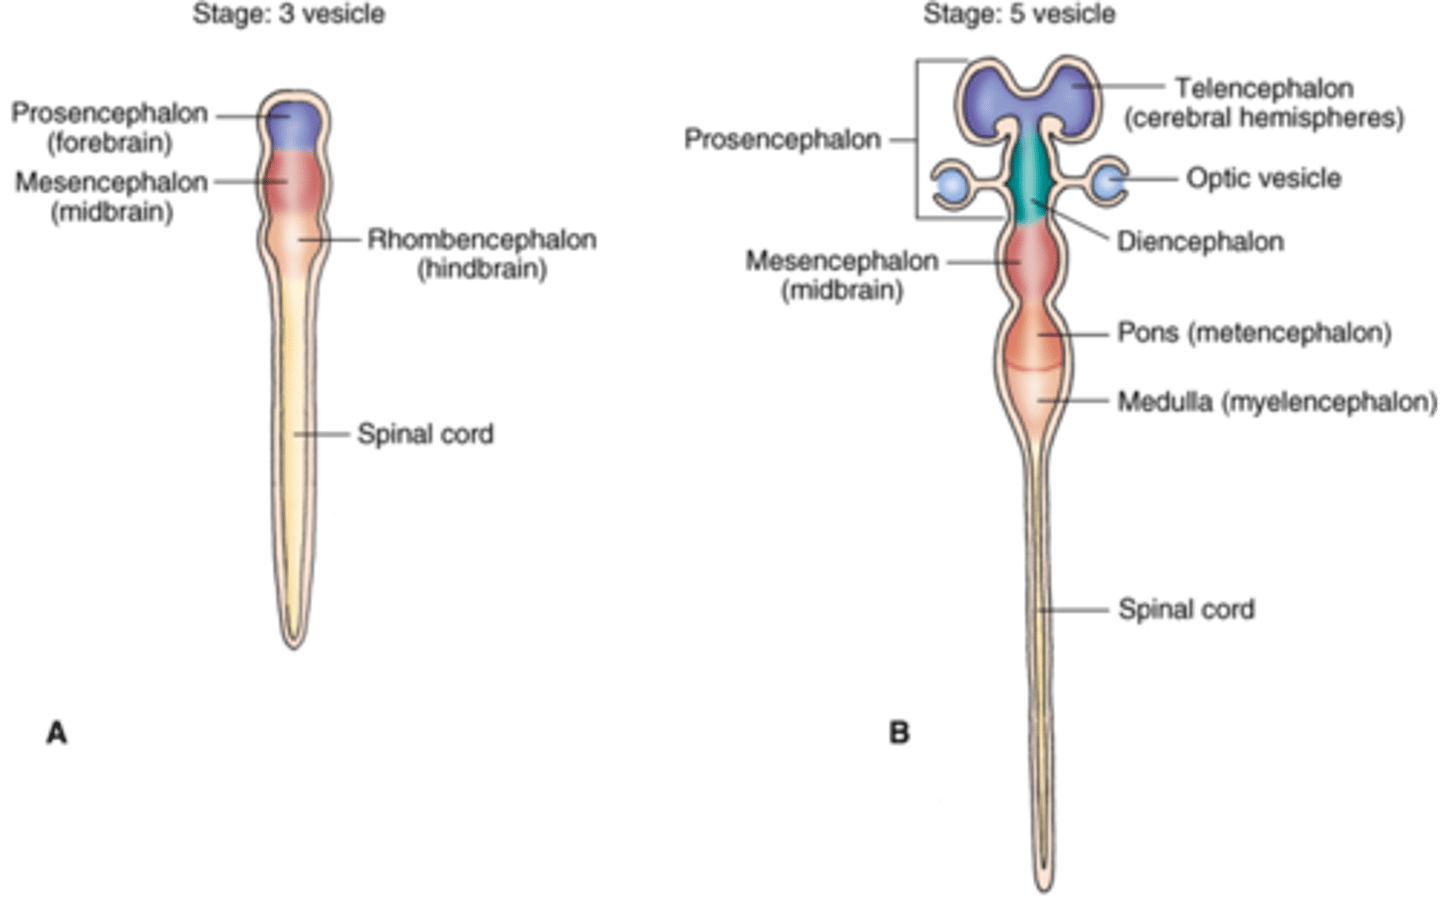

what are the 3 primary brain vesicles and the 5 secondary brain vesicles?

1. prosencephalon (gives rise to the telencephalon and diencephalon)

2. mesencephalon (gives rise to the midbrain)

3. rhombencephalon (gives rise to the metencephalon and myelencephalon)

the narrow (caudal/cranial) portion of the neural tube will form the spinal cord while the broad (caudal/cranial) portion forms the brain vesicles

caudal, cranial

The long axis of the CNS changes at the ________ _______ so that the eyes and the face are oriented forward.

The long axis of the CNS changes at the midbrain-thalamic junction so that the eyes and the face are oriented forward.